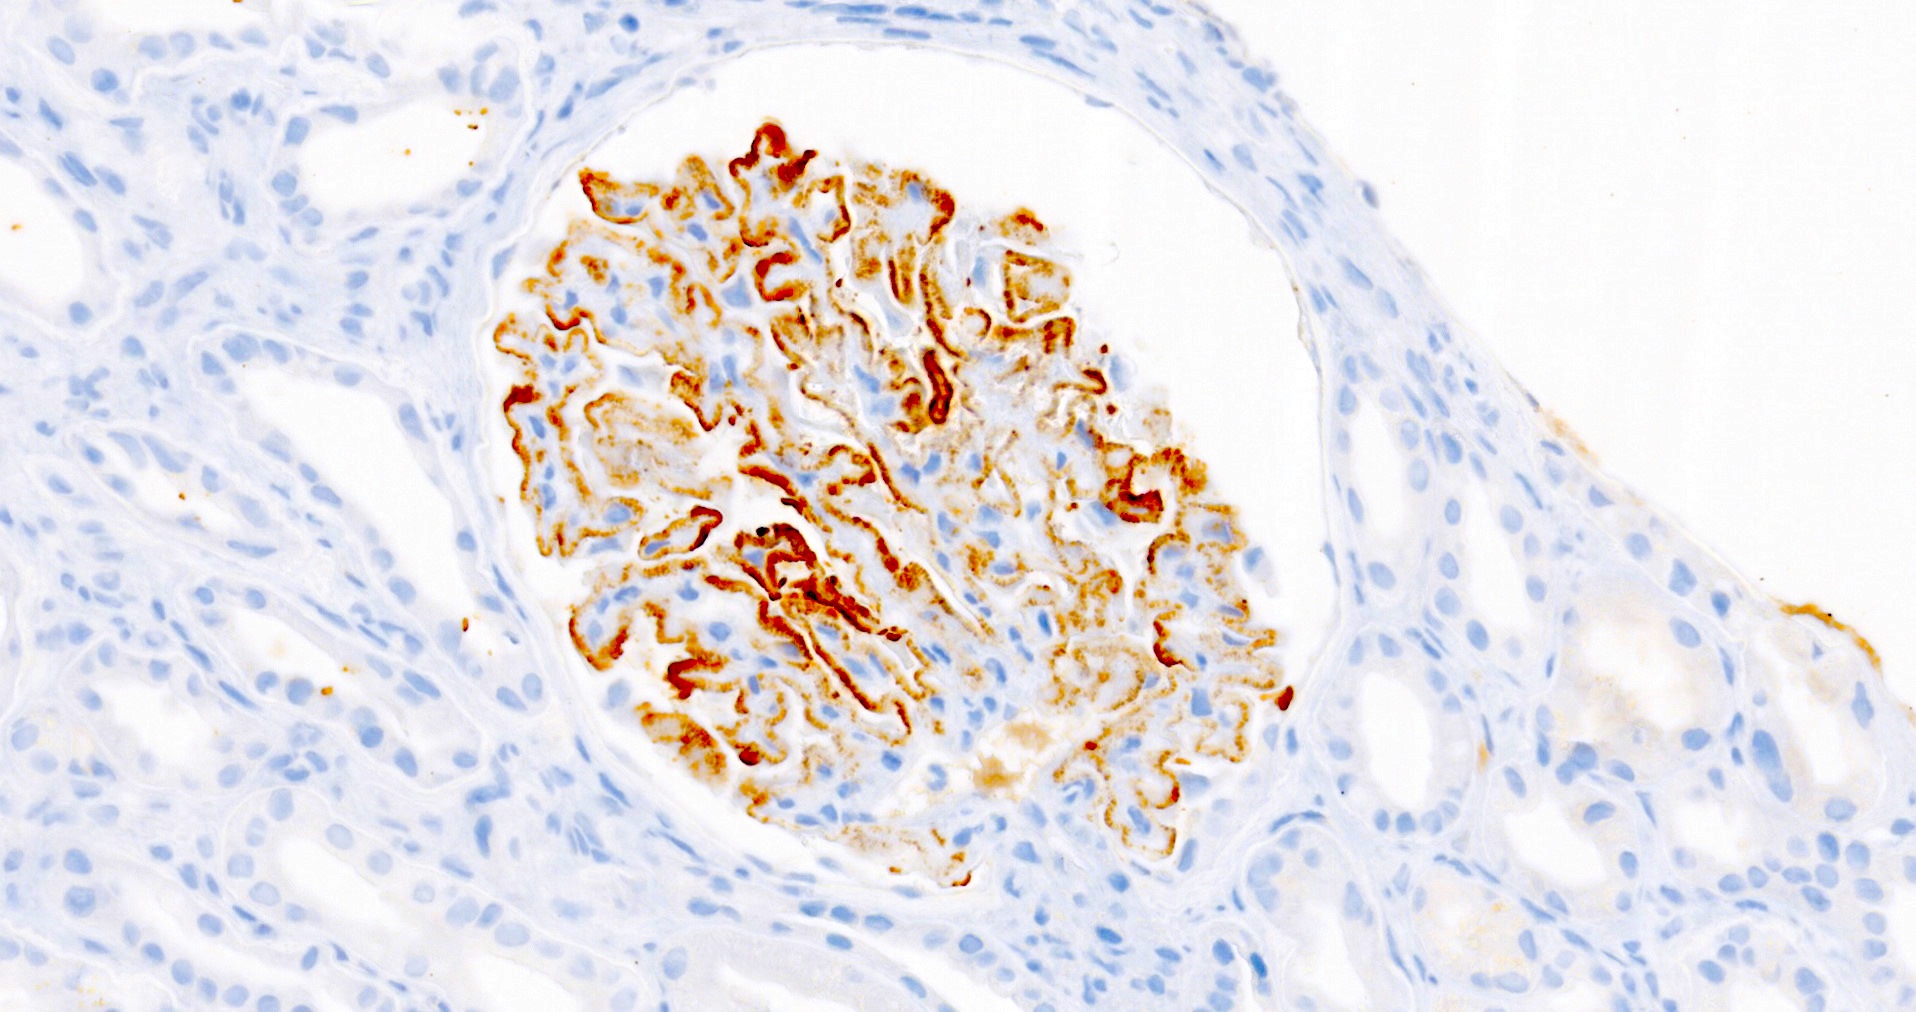

Microscopic (histologic) images

Microscopic (histologic) description

- Glomeruli may appear entirely normal in early disease (stage 1)

- Thickening of glomerular basement membrane

- Subepithelial spike formation or vacuolated appearance on PAS or Jones silver stain (Colvin: Diagnostic Pathology - Kidney Diseases, 2nd Edition, 2015, Zhou: Silva's Diagnostic Renal Pathology, 2nd Edition, 2017)

Positive stains

- PLA2R and IgG4: intense global and granular staining of glomerular basement membrane (Appl Immunohistochem Mol Morphol 2021;29:414)